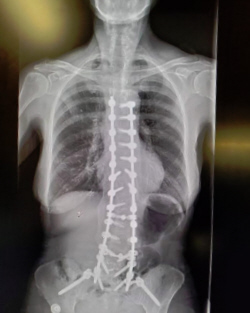

I was wearing a custom brace made of styrofoam and plastic. I wore it 24 hrs a day for a month then after just when I was up. I took it off after 2 months. This picture was taken at my first outing, 6 weeks after the surgery.